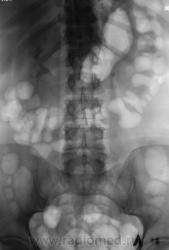

Пациент направлен на внутривенную урографию.

Камень в левом мочеточнике.

В верхней трети.

Мне кажется, неправомочно говорить о камне мочеточника слева, т.к. не видим контрастирования собирательной системы левой почки.Последний снимок выполнен на 15 минуте, конечно надо было выполнить снимки на 40 минуте , а может быть в дальнейшем и позже по времени.

Конечно есть. Да, и "блок" левой почки свидетельствует, да и УЗИ подтвердило.

Но, это история. "Родил", в страшных муках, пациент этот камень. Лечащий врач сегодня утречком продемонстрировал - большая мерзость, эти камешки, почти - "кактусы".

Валентин Львович, можно вопрос: почему нет контраста в левой почке вообще, а с ним и гидронефротической трансформации почки?!

На мой взгляд, гидронефроз еще не развился. Камень, по всей видимости "вывалился" из одной малой чашечки и застрял, вызвал "почечную колику" и поплыл делать своё доле дальше - дистально по мочеточнику. Я вообще сомневался в контрастировании полых систем, так как исследование было проведено на "высоте" почечной колики.